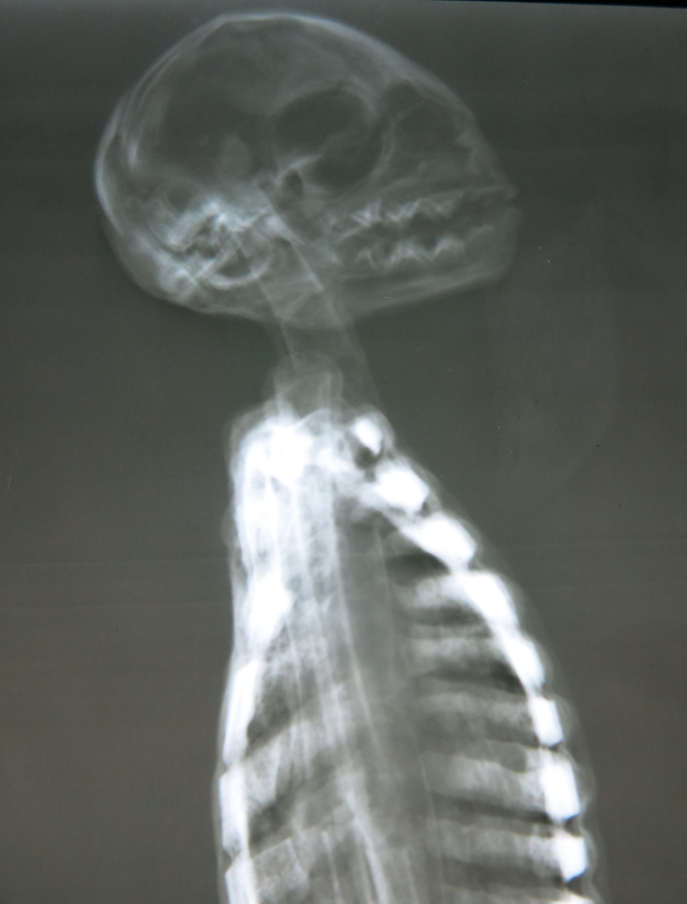

▲外星人木乃伊的頭骨顯然取自其他動物

按照莫桑的説法,這些“外星人木乃伊”存在完整的內部構造,但經過X光照射分析,這些所謂的外星人全都是粗製濫造的假貨。事實上,所謂的木乃伊確實存在“骨骼結構”,但明顯不是自然生長的,而是用人和動物的骨骼拼裝而成的。脊柱、肋骨和肢體全部都是用折斷的鳥類骨骼拼在一起的,而且沒有任何關節相互連接。其中一個代號“E.V.”的木乃伊頭骨取自某種小型動物,另一些外星人的頭骨則取自猴子和美洲駝。

▲這個頭骨取自美洲駝的後腦